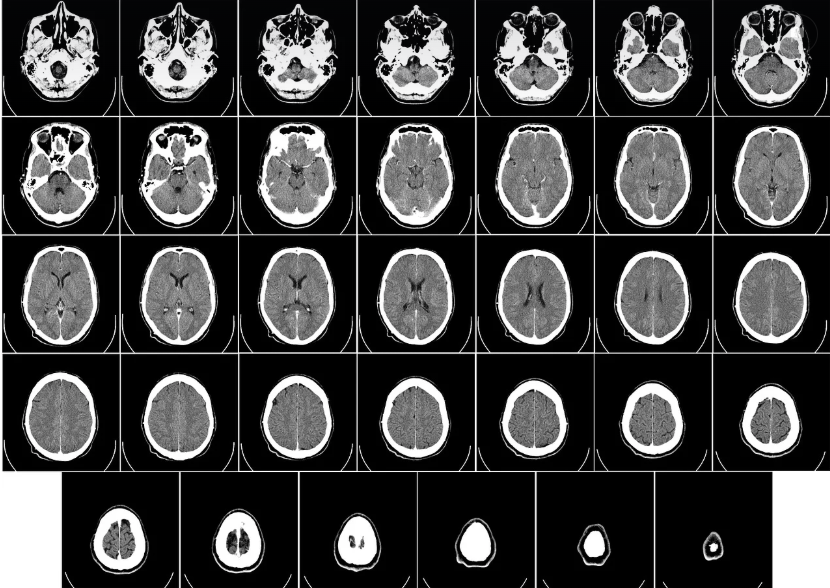

CT(Computed Tomography)는 X-ray를 다양한 각도에서 촬영한 뒤, 컴퓨터로 영상을 재구성해 인체의 단면 이미지를 얻는 검사 방법입니다. 일반 X-ray보다 훨씬 더 정밀하게 내부 장기와 조직을 확인할 수 있어, 종양, 출혈, 장기 손상, 골절 등 다양한 질환의 진단에 사용됩니다.

일반 X-ray는 2차원 평면 이미지만 제공하는 반면, CT는 단면 영상을 통해 더 입체적이고 정확한 정보를 제공합니다. 특히, 복잡한 구조의 장기나 조직을 분석할 때는 CT가 훨씬 유리합니다.